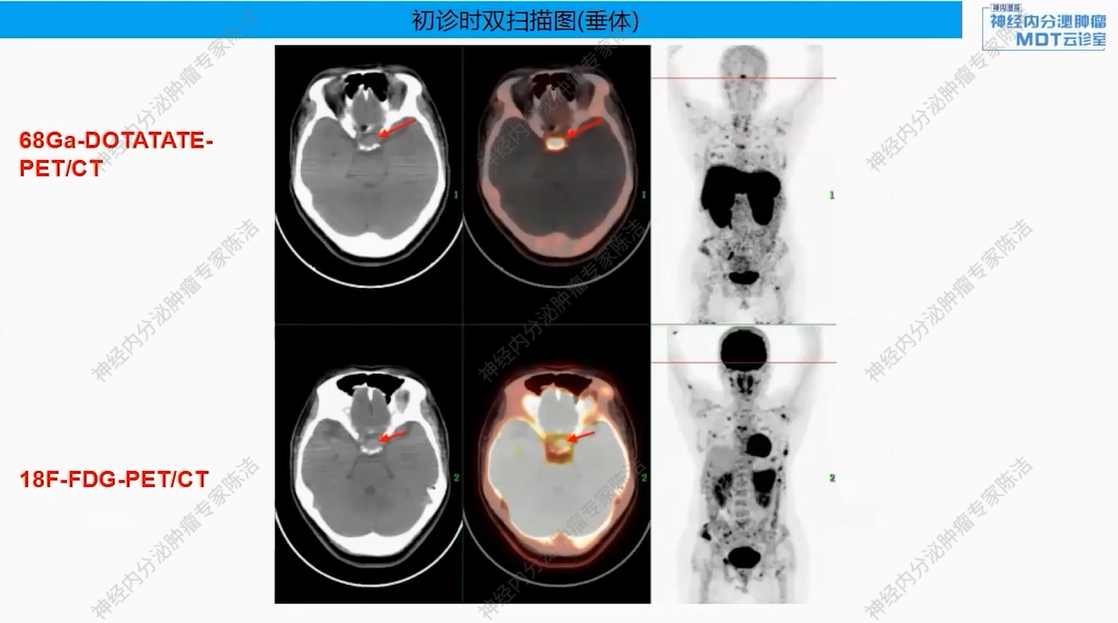

18F-FDG-PET-CT提示:胰尾部见巨大肿物(约8.6*7.2*7.8 cm),FDG代谢明显增高。胰体部另见一小结节(约0.8*0.7 cm),FDG代谢轻度增高。全身多发骨质改变,FDG代谢增高。

68Ga-DOTANOC-PET-CT提示:胰尾部巨大肿块,DOTANOC摄取阴性;胰体部小结节,DOTANOC摄取阳性。甲状旁腺区多发结节,DOTANOC摄取阳性;垂体区稍增大,DOTANOC摄取阳性。

核医学科徐俊彦教授:本病例双扫描PET显像体现了该患者多发肿瘤间异质性。胰尾大病灶(胰岛素瘤)呈SSTR阴性、FDG阳性,这符合约50%胰岛素瘤不表达SSTR的特征。而胰体小病灶呈SSTR阳性、FDG轻度增高。垂体区在SSTR(有生理性摄取)和FDG(无生理性摄取)上均呈阳性,提示垂体瘤可能。骨骼病灶呈SSTR和FDG“双阳性”,高度提示为SSTR阳性的NET转移,但建议对于骨病灶,可对相对表浅的病灶行骨穿以进一步明确骨病灶情况。从最初影像可见髂骨存在明显骨质破坏,甚至骨皮质整体受损,因此骨转移的可能性较大。然而,鉴于该患者同时患有甲状旁腺瘤,甲状旁腺瘤常伴发棕色瘤改变,故目前不能排除甲状旁腺继发的骨改变的可能。

该患者以低血糖为首发症状,影像学发现胰腺占位、甲状旁腺及垂体病变,并检测到MEN1胚系基因大片段缺失而最终确诊。胰腺上同时存在SSTR阴性的胰岛素瘤和SSTR阳性的神经内分泌肿瘤,且骨转移灶(SSTR阳性)极可能来源于后者(胰体小病灶),而非引起主要症状的前者(胰尾大病灶)。